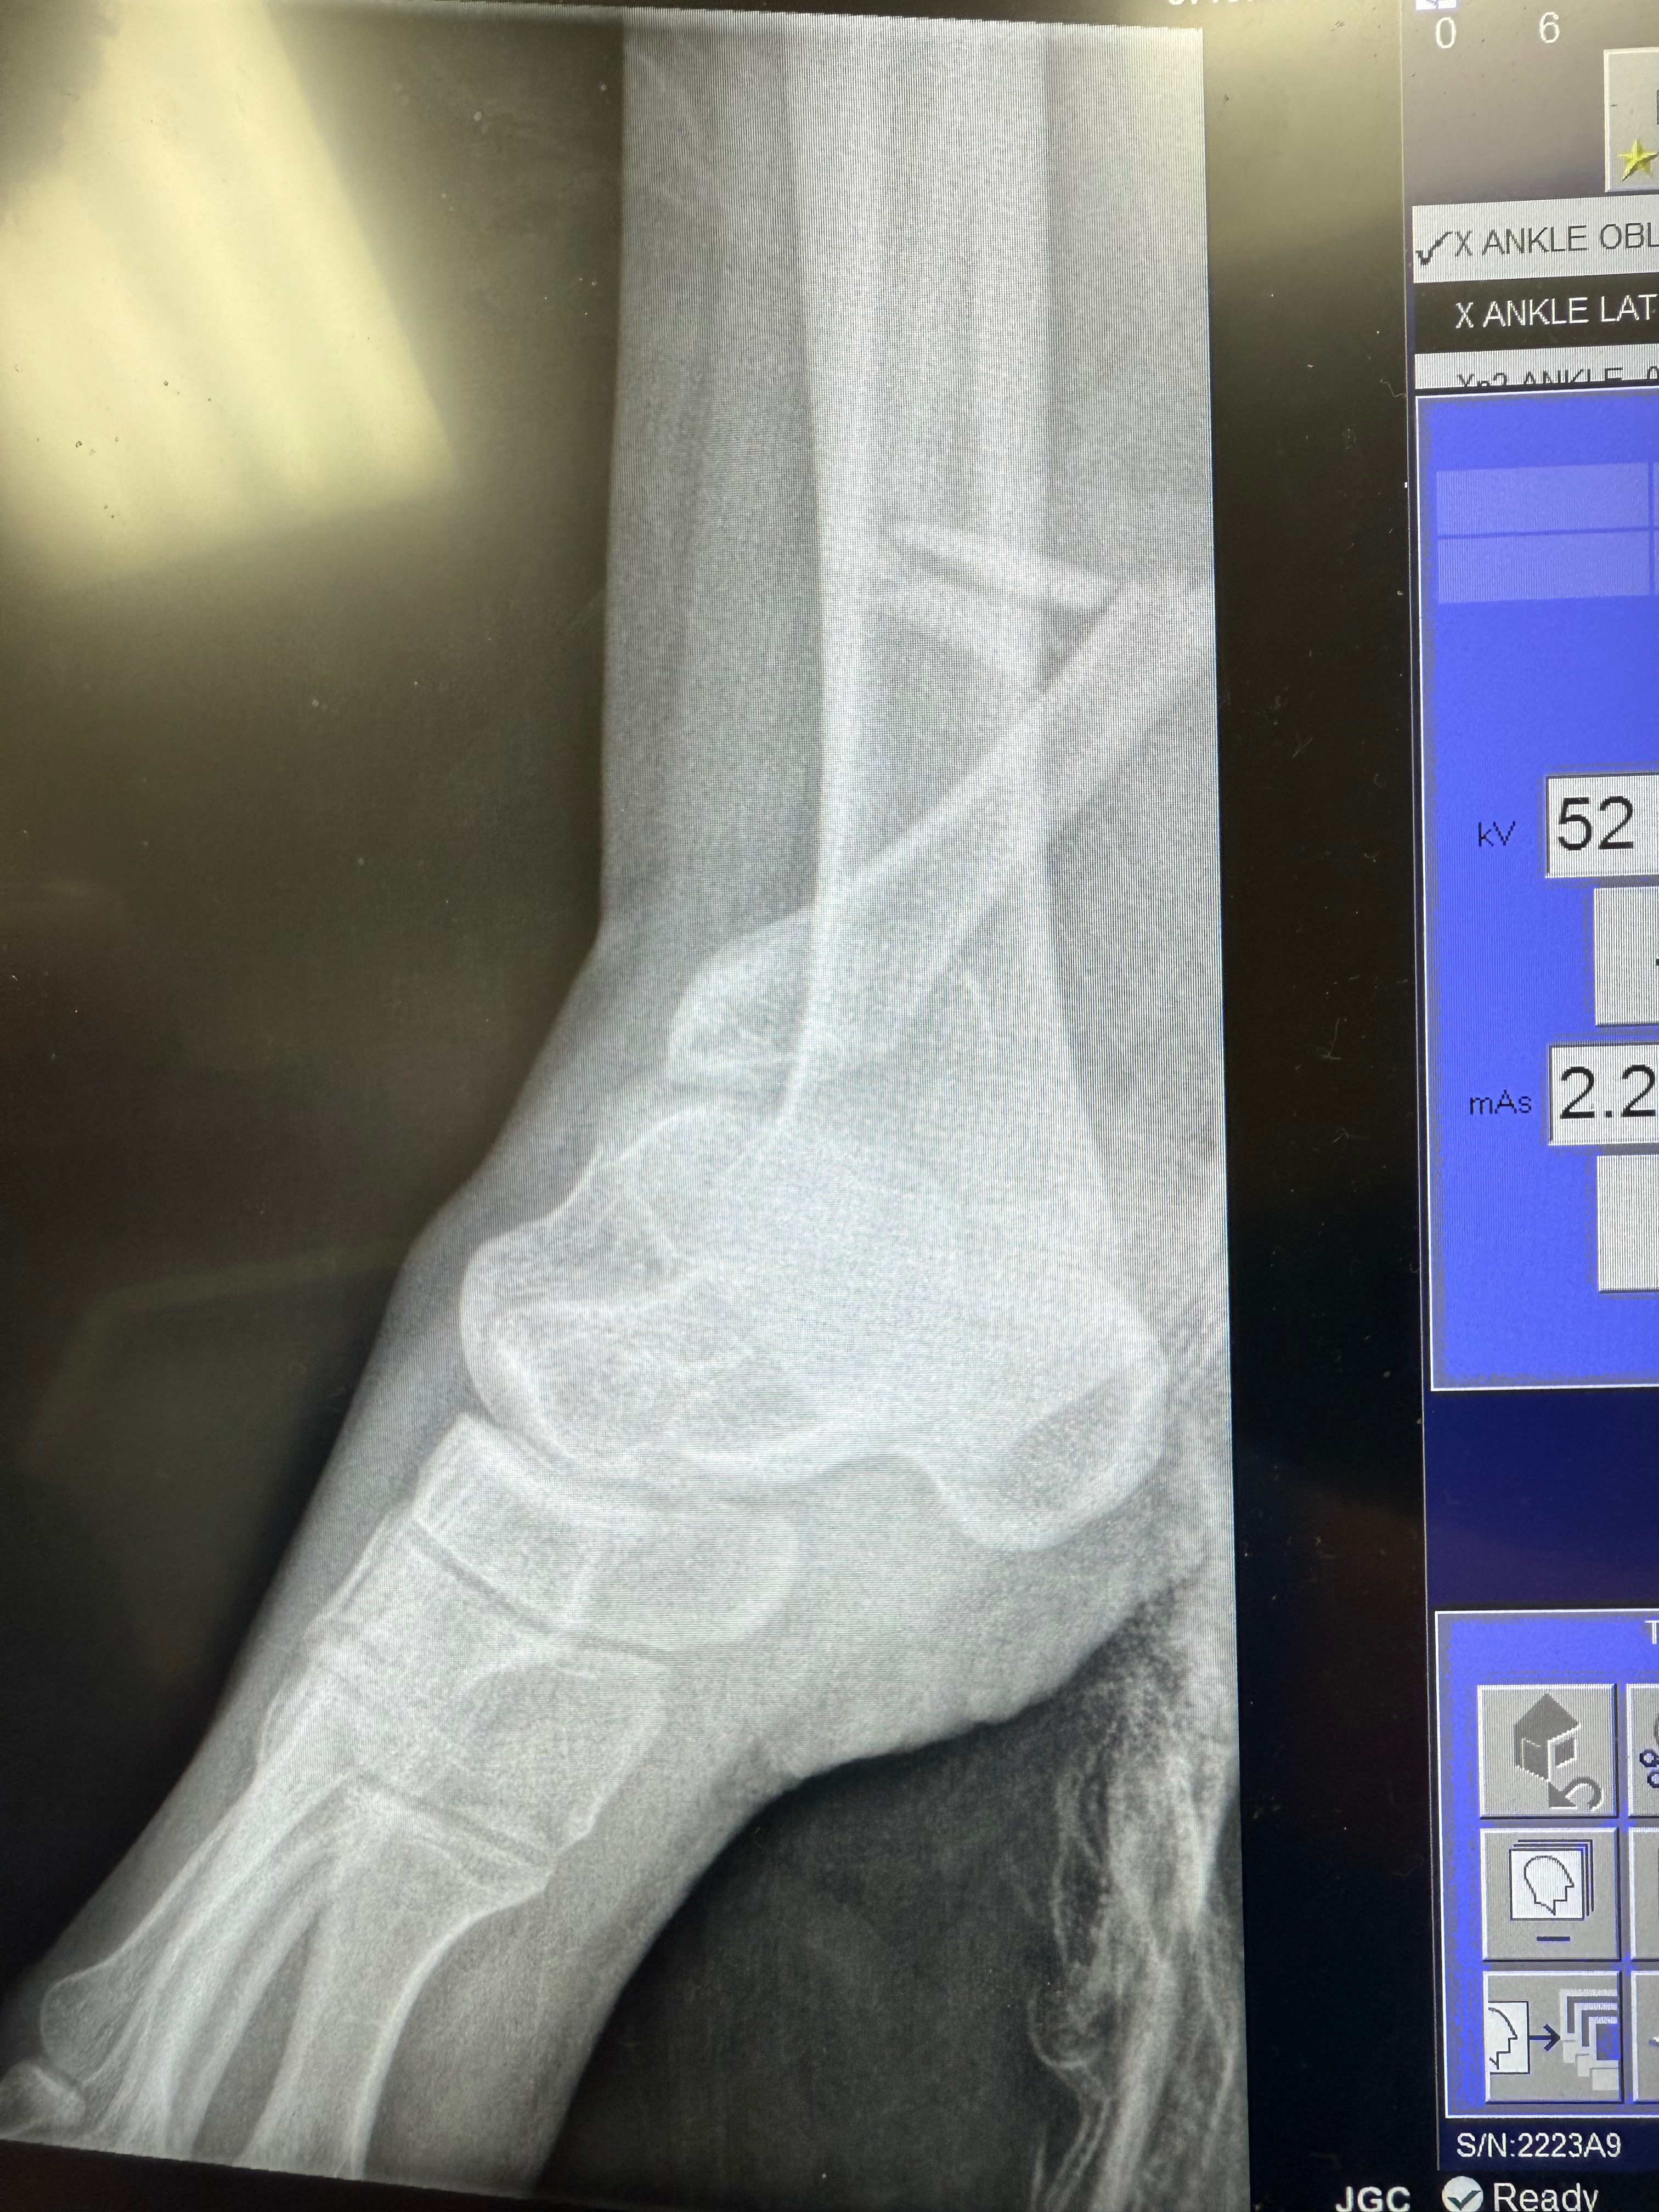

Hi, I’m Marianne McDonald, Annica’s (Annie) mom. On Sunday, June first, Annie was in a life-changing car accident. She was lucky to walk away with her life, and we are very grateful God had more for her to do in life. Annie suffered serious damage to her right leg. They were able to save her foot, but she cannot even put weight on it for 8 weeks. Her left ankle is also broken. Due to the trauma and mostly being bedridden for some time, she is on blood thinners to reduce the risk of stroke and pulmonary embolisms, which are life-threatening. Annie now requires round-the-clock care at home. I tried to have insurance in place to avoid having to ask for outside help, but unfortunately, her being disabled and needing at-home care from me wasn’t covered. I was eligible for leave from work, but it’s unpaid. We also have many medical bills outside of insurance coverage and other costs, including replacing my vehicle, that were unexpected to come all at once. As I eat my humble pie (this coming from a very independent woman), I ask for help so I can be home with her to care for her. Everyone’s support has been unfathomable so far. I appreciate each and every one of you, and so does Annica.